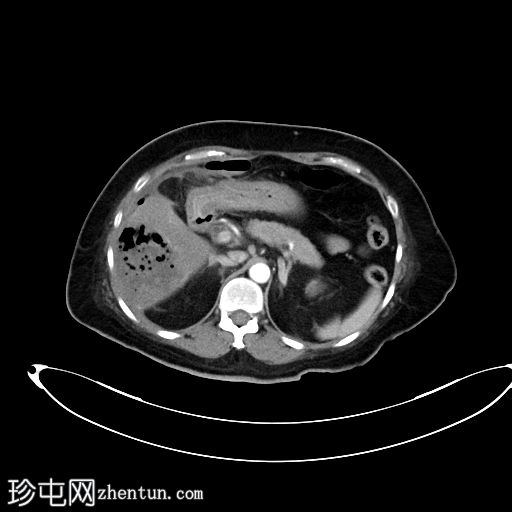

X线检查

右侧膈肌下方可见斑驳状气体影。

野清晰。无胸腔积液。心纵隔边界正常。

对于发热患者,若在右侧膈肌下方发现斑驳状气体影,放射科医生应考虑气肿性肝脓肿的诊断。鉴别诊断包括膈下脓肿。门静脉积气或胆道积气的可能性较小,因为它们呈管状。其他良性鉴别诊断包括 Chilaiditi 综合征。